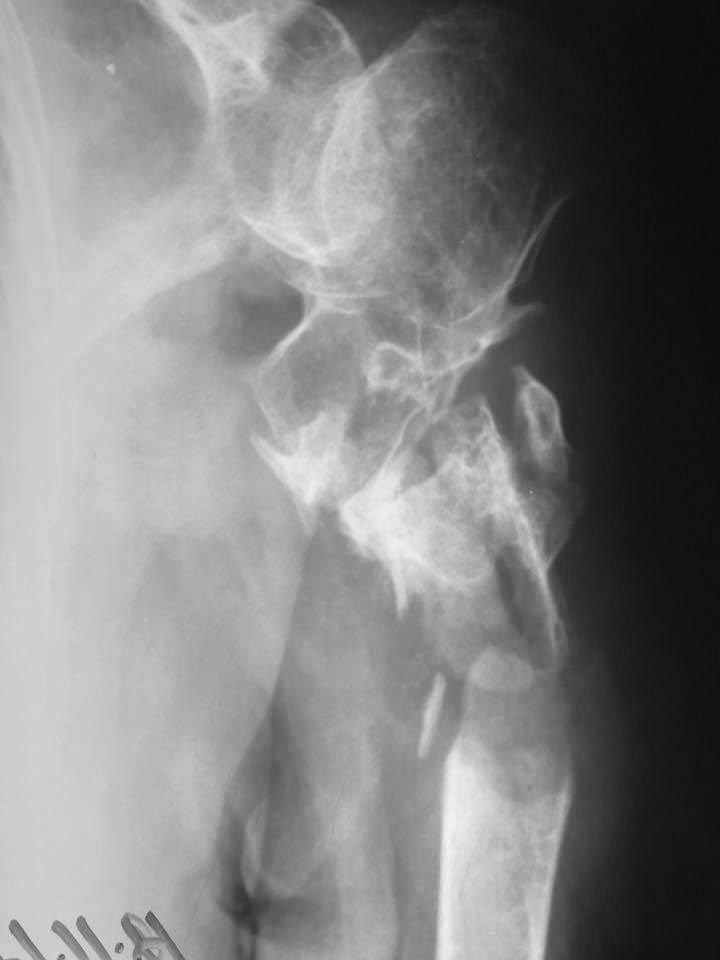

Новый перелом на фоне несращения плеча

Уважаемые коллеги, подскажите ...... в принятии решения? Первая травма 2 года назад. Вторая 2 недели.